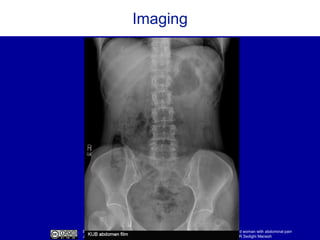

Imaging

CT abdomen/pelvis with contrast

Surgically absent gallbladder, appendix,

and uterus; otherwise normal.